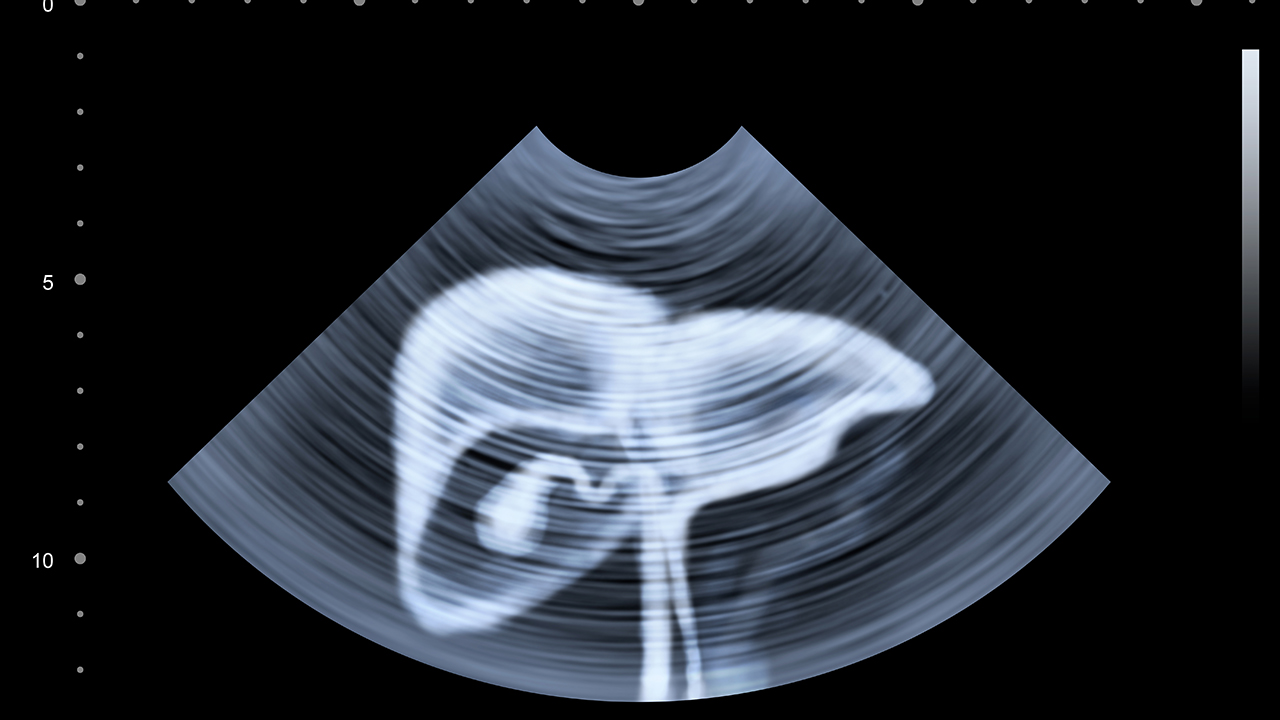

肝癌的预防与健康管理至关重要。建议定期进行肝功能检查和肝脏超声检查,尤其是慢性肝炎患者和高危人群。保持良好的生活习惯,避免酗酒和食用霉变食物。接种乙肝疫苗可有效预防乙肝病毒感染,降低肝癌风险。对于已确诊的肝癌患者,应积极配合治疗,定期复查,保持良好的心态和营养状态,提高生活质量。